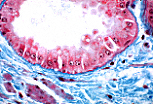

| 光镜下,构成该腺泡的浆液性腺细胞可通过以下特征识别:基底部嗜碱性、细胞核呈圆形且位于细胞基1/3处、顶端区域有嗜酸性的分泌颗粒(酶原颗粒)。 | |

酶原颗粒稳定性较差,在显微制片过程中常难以完整保存。在本图像中,仅能辨认出取样时这些颗粒所处的位置。

圆形的细胞核是区分浆液性腺细胞与黏液性腺细胞的特征。 |

| 在该浆液性腺泡中,细胞顶端可见细胞间小管。这些细胞间小管增大了发生胞吐作用的顶端表面积。 | |

| 浆液性腺细胞合成酶原,其特征为:基底部有高度发达的粗面内质网、圆形细胞核、核上区的高尔基体(该电镜照片中不可见),以及顶端的分泌小泡。粗面内质网的大量存在,是光镜下观察到细胞基底部嗜碱性的原因。 | |